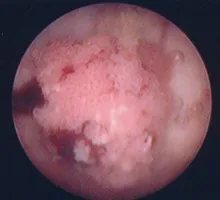

地図状舌写真で見る「子どもの病気」 - みやけ内科・循環器科。

地図状舌 - Wikipedia。